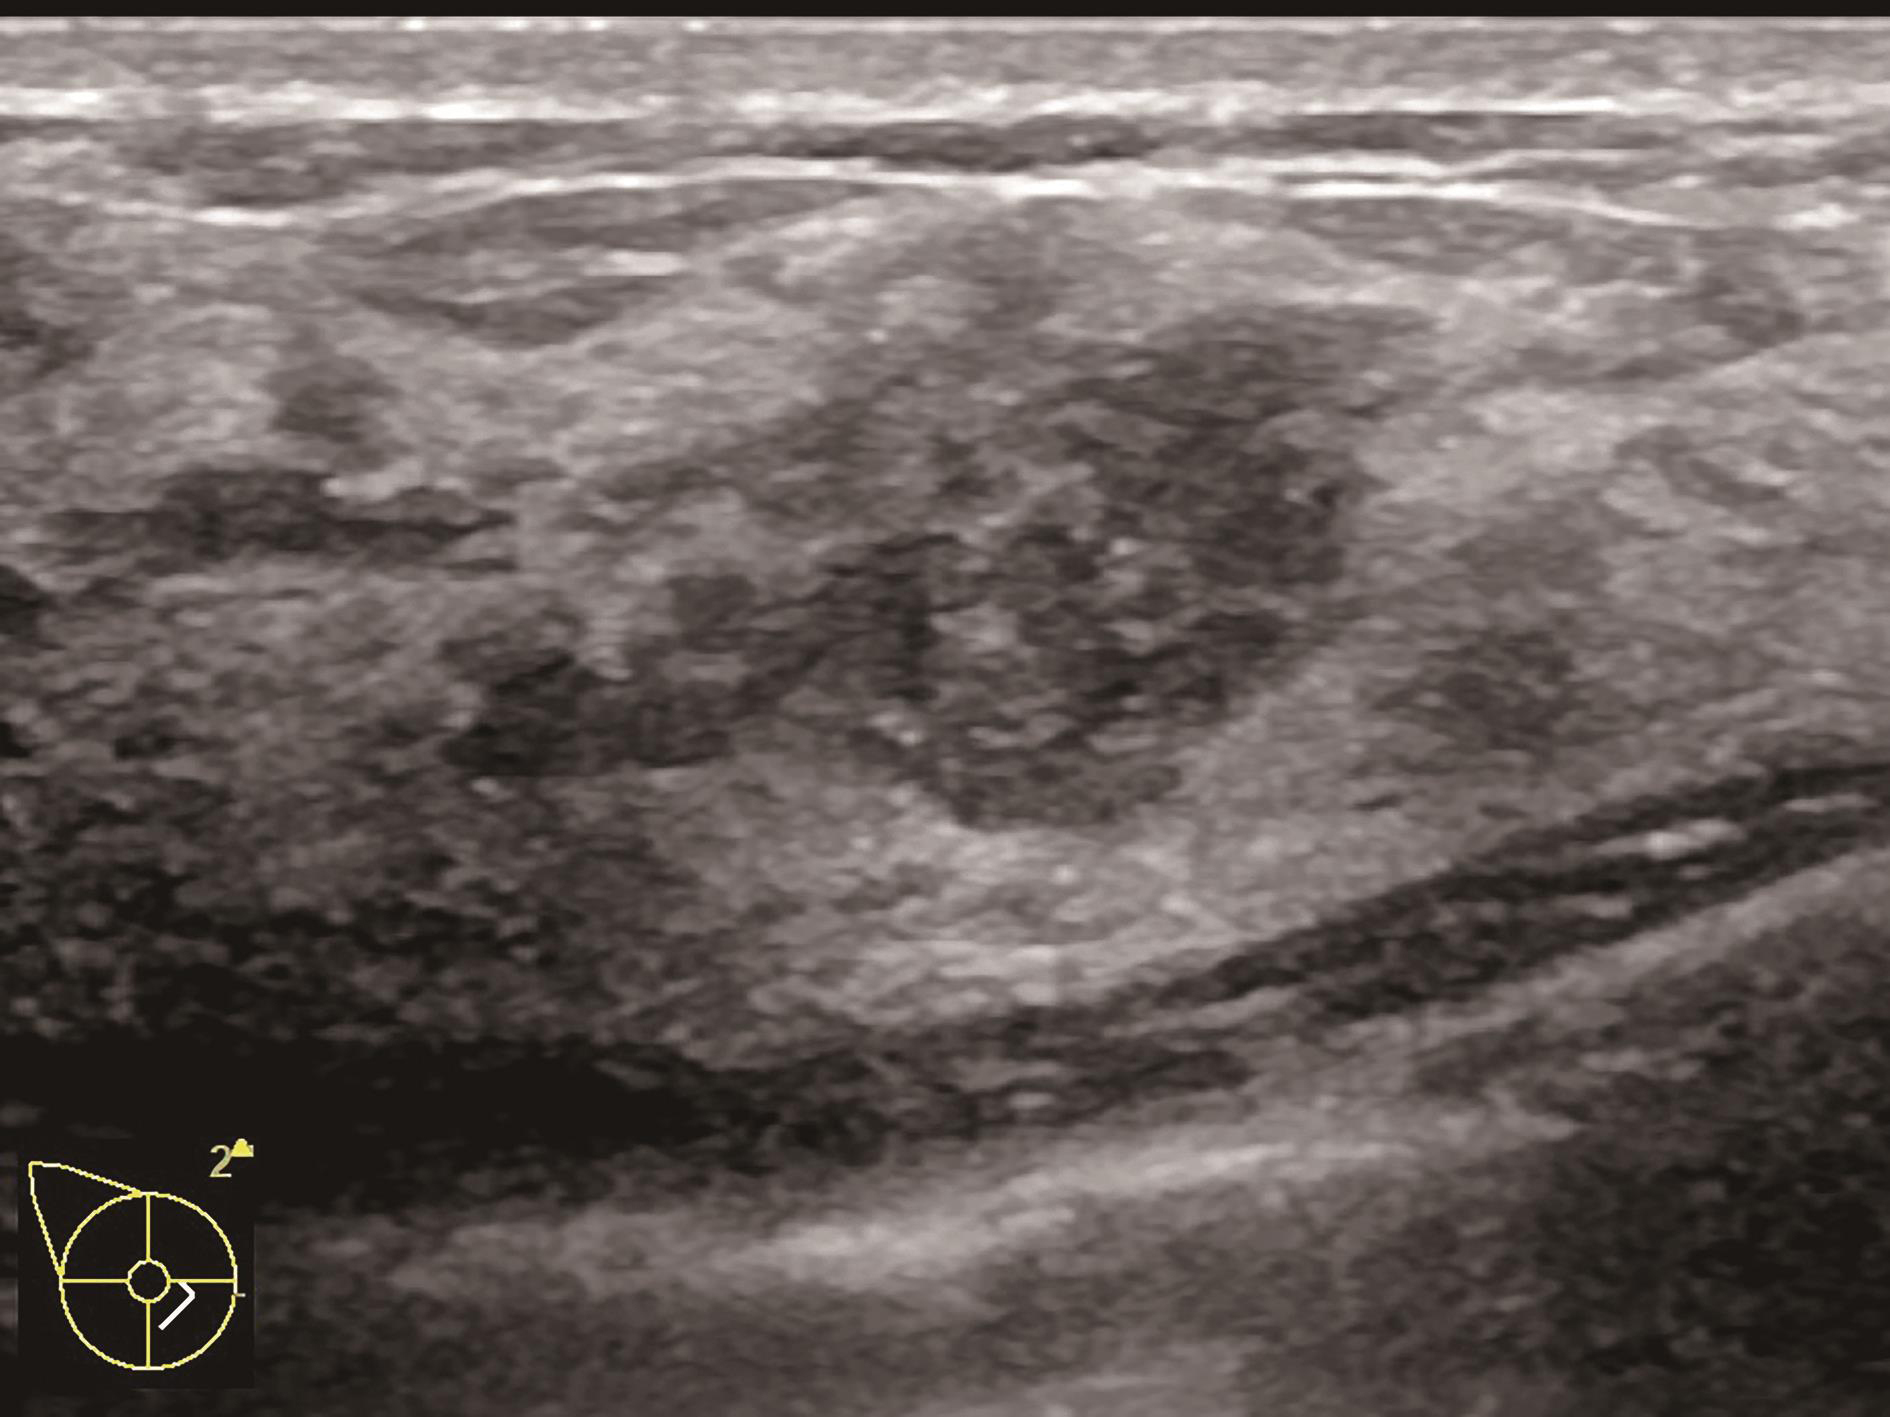

A.病灶二维图像;B、C.病灶CDFI图像;D.同侧腋窝淋巴结情况;E.病灶弹性成像图像

图2-2-1 确定造影病灶

图2-2-3 病灶最大切面

图2-2-4 纵横比大于1或边界最不规整切面

图2-2-5 血流信号最丰富或有滋养血管切面